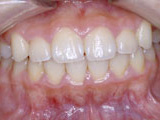

症例1:乱ぐい歯「歯並びが乱れている」

治療前